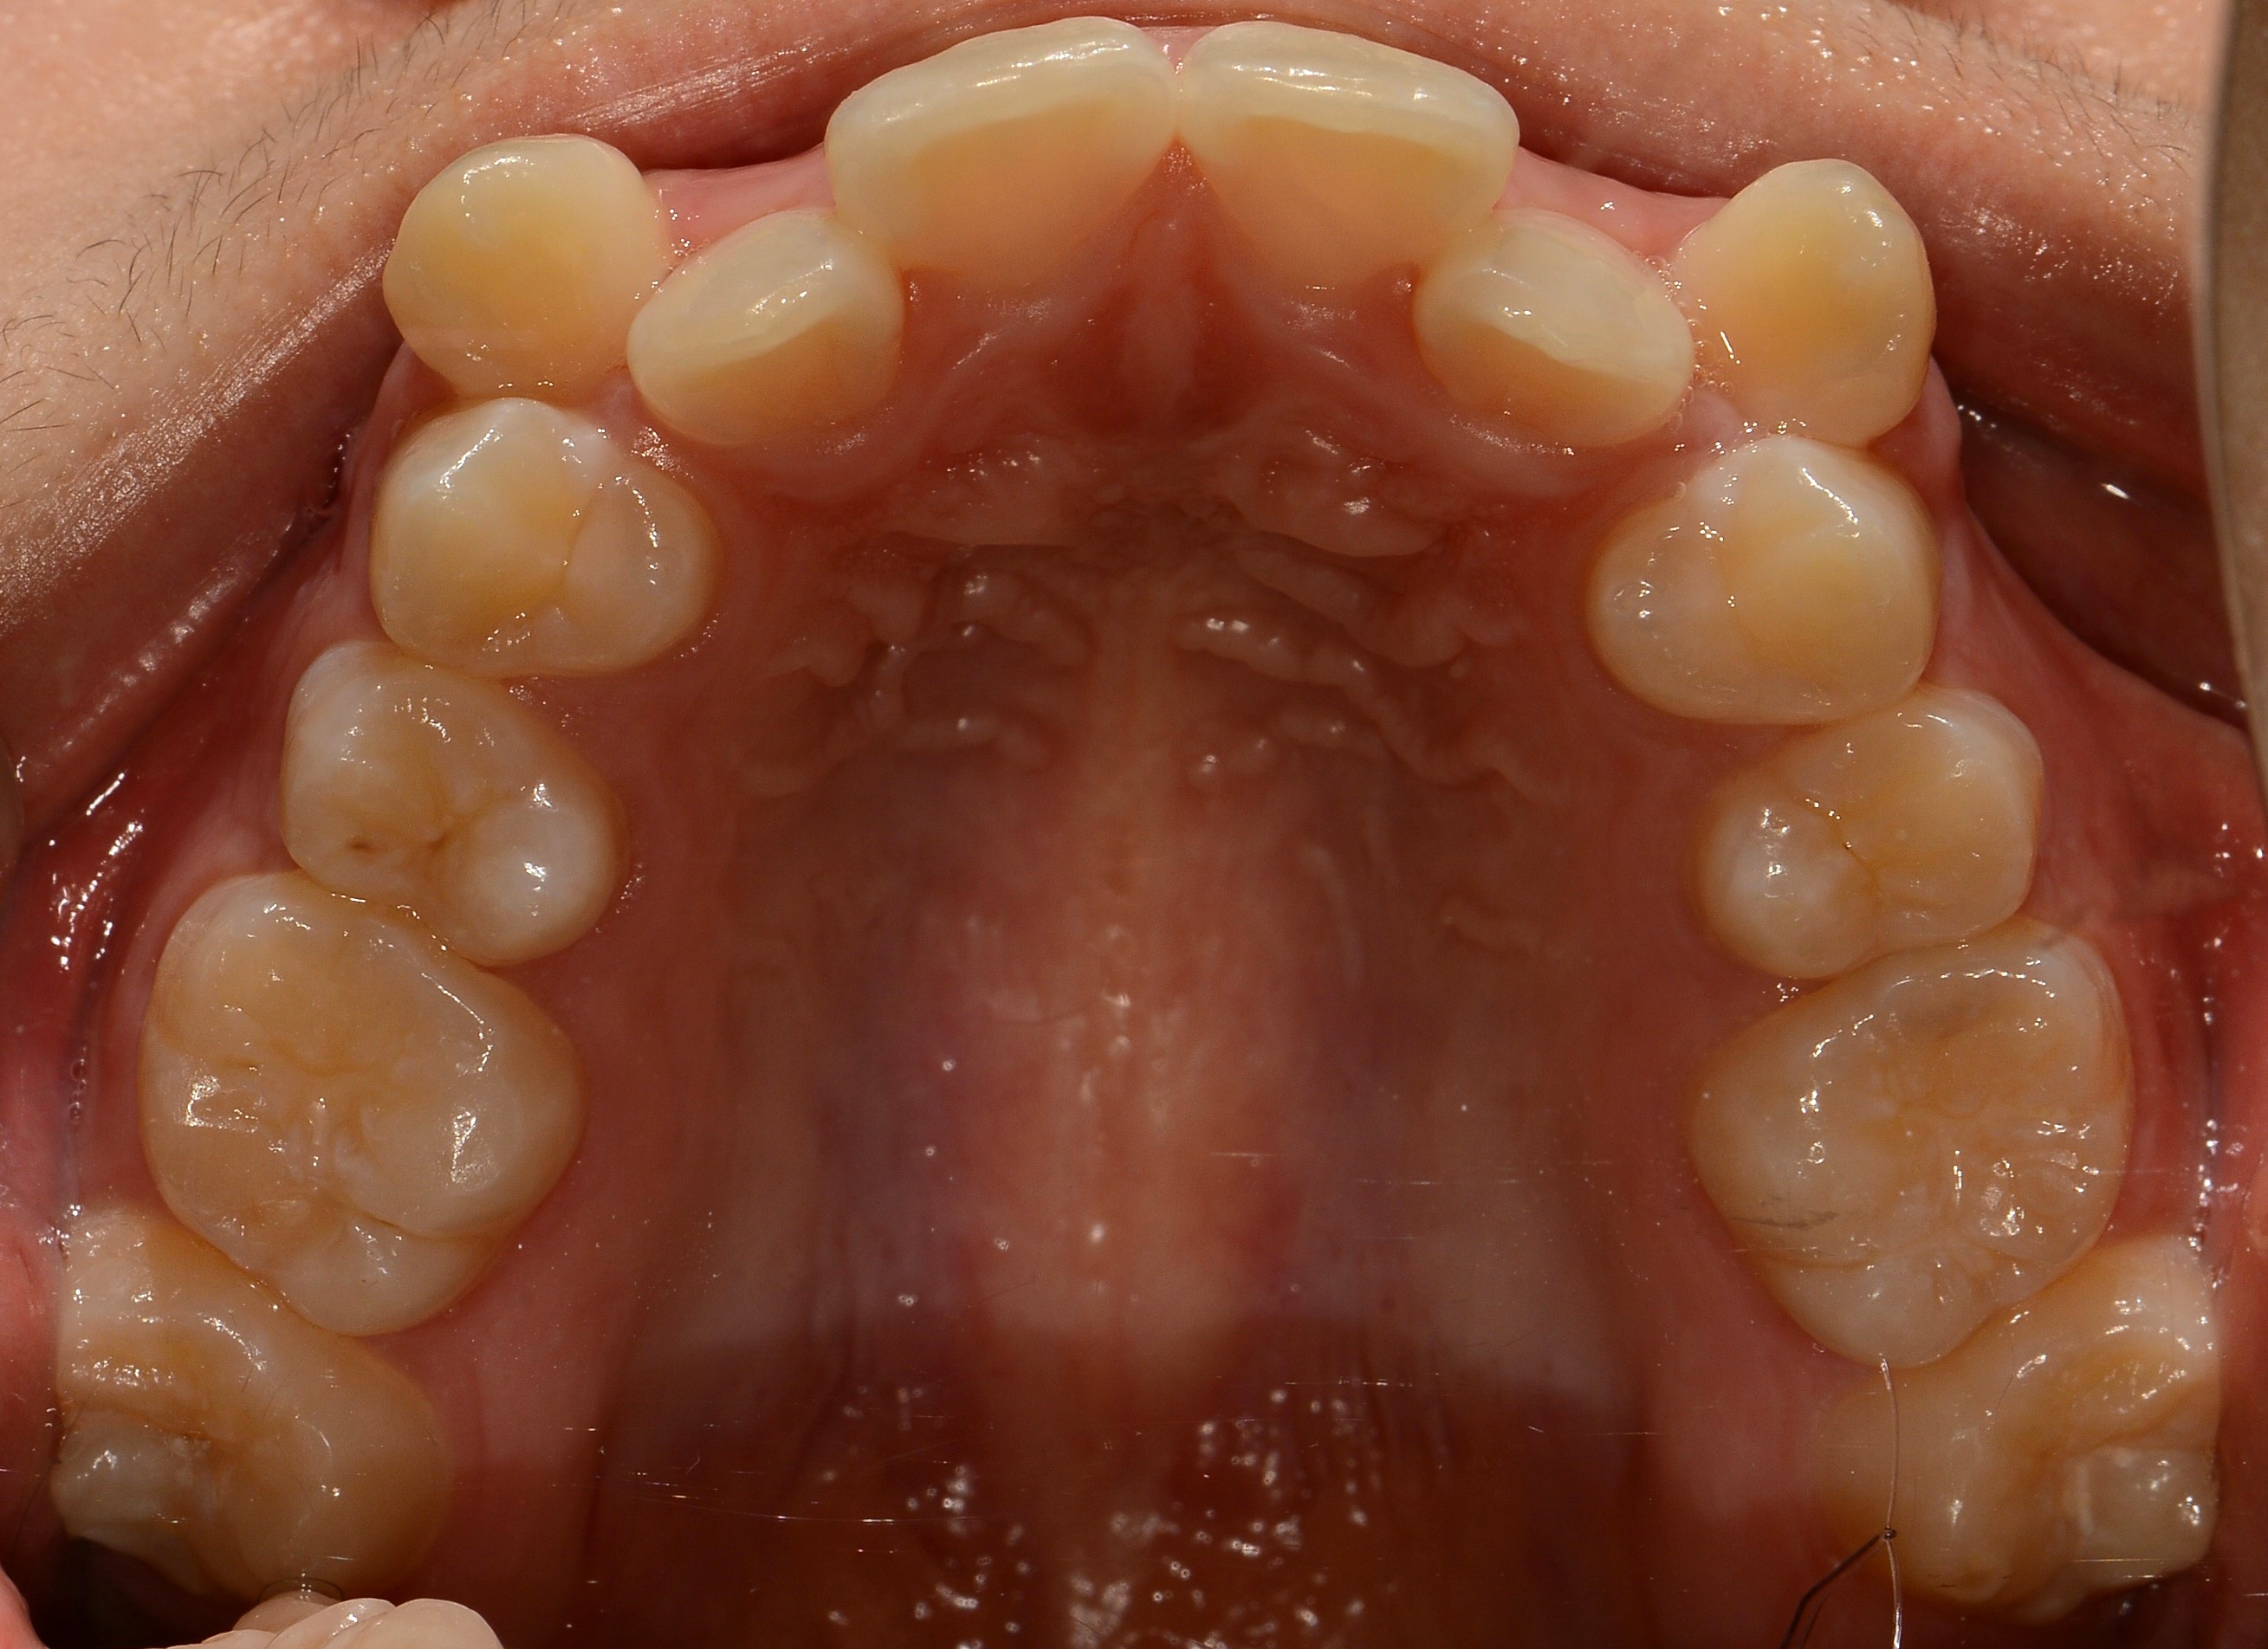

치료 전 사진입니다.